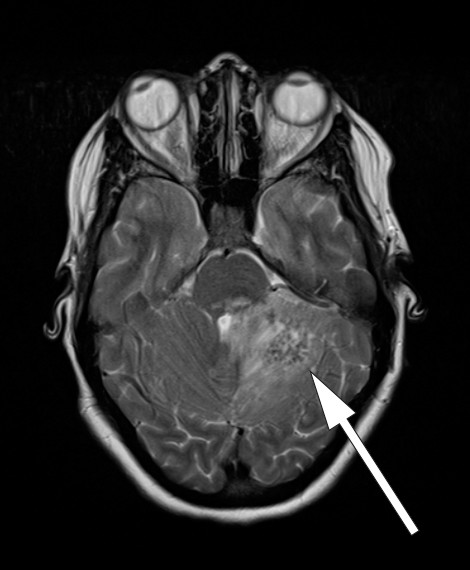

Dag 6 ble hodepinen verre, i tillegg så man parese av n. abducens. Pasienten var vedvarende febril, temperaturen lå mellom 38,0 °C og 38,5 °C. Ny CT caput med kontrast viste kontrastoppladning ved tentoriet, i cerebellum, i pons samt i høyre oksipitallapp med omkringliggende ødem (fig 2). MR cerebrum uten kontrast viste lavt signal på T2-vektet sekvens, tilsvarende de kontrastladende lesjonene (fig 3).